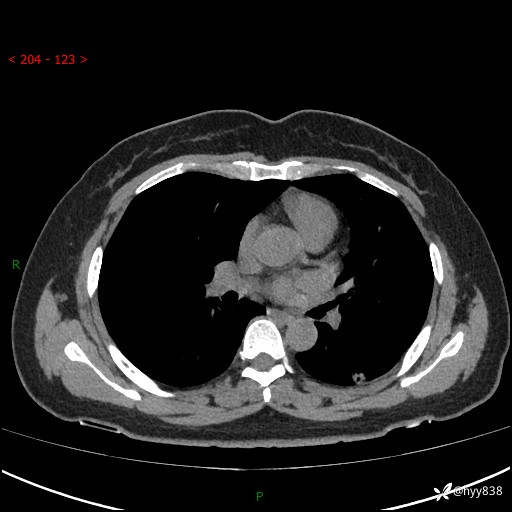

胸部CT平扫(2023.3)